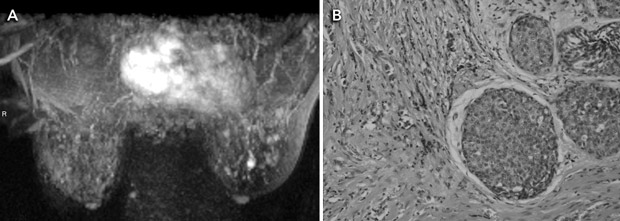

MRI is a highly sensitive test for detecting breast cancer. It is not recommended for screening women at average risk because it is associated with substantial numbers of false-positive results and cost. It has been proposed as adjunct screening for women with a genetic predisposition to breast cancer (Box 3). Mammography has lower sensitivity in this group, detecting fewer than half the breast cancers diagnosed.12

A meta-analysis of five studies of MRI as an adjunct to conventional imaging in high-risk women has provided convincing evidence that MRI detects additional cancers, with an incremental sensitivity of 58% (95% CI, 47%–70%) compared with mammography alone.15-20 Incremental sensitivity was lower when MRI was added to mammography combined with ultrasound examination (44%; 95% CI, 27%–61%) or to mammography combined with ultrasound plus clinical breast examination (range, 31%–33%).15 As summarised in Box 4, the addition of breast MRI led to the earlier detection of eight to 24 additional cancers per 1000 screens.15-20 Differences in MRI yield across studies reflected differences in comparator screening (mammography with or without ultrasound and clinical examination) and variations in disease prevalence. MRI provided the highest cancer yield when used in patients at highest risk.

The effect of detecting MRI-positive (mammogram-negative) cancers on breast cancer mortality, treatment morbidity or the incidence of interval cancers among high-risk (predominantly young) women has not yet been measured. Reductions in breast cancer mortality observed in trials of mammography screening among older, average-risk women have been attributed to the detection of breast cancer at an earlier stage, when the disease is more amenable to treatment. It is not yet clear whether earlier detection of cancers by MRI will bring the same benefits to high-risk women, who may represent a different prognostic group. Accuracy studies comparing tumour size and lymph-node spread between the extra cases detected by MRI and cases detected by conventional imaging alone have not provided consistent evidence that MRI produces a significant stage shift in the detection of breast cancer.15

MRI also increases the likelihood of recall for investigation of false-positive findings, although the evidence is not consistent across studies. Two studies observed that the addition of MRI produces at least a threefold increase in risk of undergoing percutaneous needle biopsy (PNB) for benign findings.17,18 One of these studies also reported a twofold increase in risk of surgical biopsy for benign findings.17 Another study did not find a significant difference in the rate of PNB when MRI was added to mammography, but did not report data on surgical biopsy.16

We thank Dr Ruth M L Warren (Department of Radiology, University of Cambridge, United Kingdom) for the MRI images.